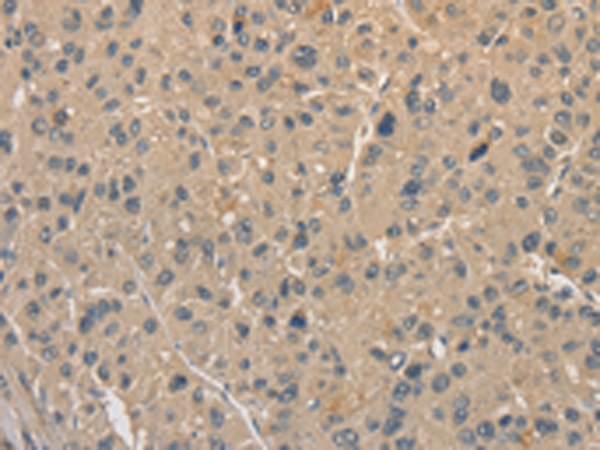

分类: 科研抗体货号: P07816别名: ALDH12; DJ352A20.2应用: WB,IHC反应种属: Human, Mouse